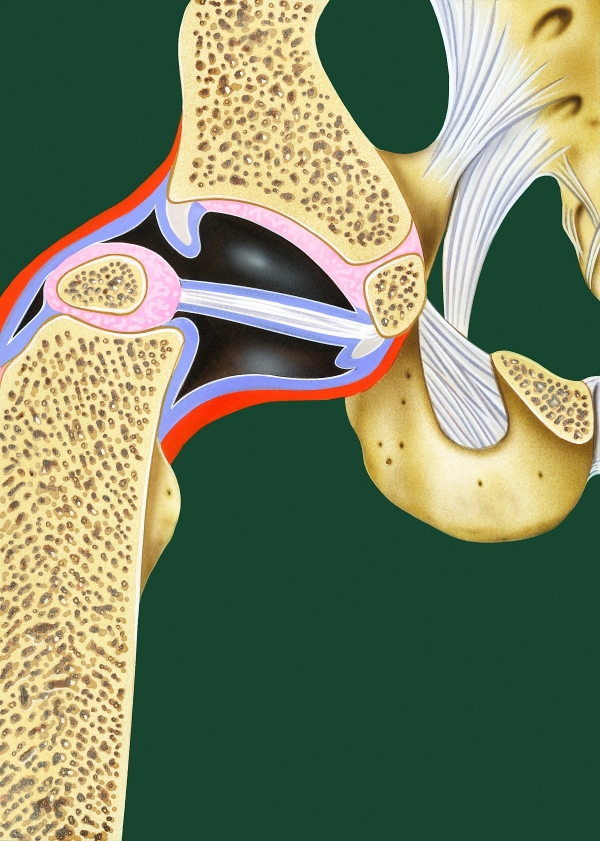

고관절이란?

고관절 통증 증상(엉덩관절)은 오른쪽과 왼쪽의 골반과 넙다리뼈가 연결된 관절의 통증을 일컫습니다. 고관절은 상체의 하중을 분산시키는 역할을 하며, 일어서거나 앉거나 일상생활에서 자주 쓰이는 관절이며 부담도 잘 받게 됩니다. 모양도 크기도 탁구공만 합니다. 일상적으로 걸을 때 고관절에 체중의 3~4.5배의 무게가 실리게 됩니다. 계단을 오를 때는 대퇴골두에 전해지는 무게는 몸무게의 8배, 달리는 경우 10배에 가까운 하중을 견뎌내애 한다고 합니다. 탁구공 크기만 한 대퇴골두가 감당하기에는 너무 무겁기 때문에 고관절이 느끼는 부담도 크고 쉽게 손상될 수 있습니다. 다른 관절과 마찬가지로 감당하기 어려운 충격이나 무게가 가해지면 고관절 통증 증상이 발생하게 되는데요. 퇴행성 고관절염, 대퇴골 골절, 대퇴골두 무혈성 괴사, 선천성 고관절 탈구 등이 대표적인 고관절 통증 질환입니다.